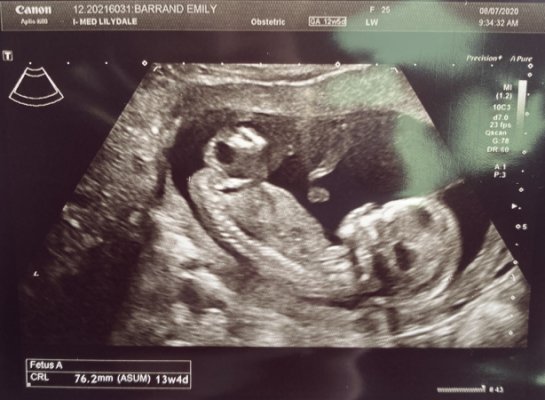

جفت قدامی یعنی جفت به دیواره جلویی رحم (سمت شکم مادر) چسبیده باشد، نه به دیواره پشتی (نزدیک ستون فقرات) یا کناره ها. این وضعیت در سونوگرافی به راحتی تشخیص داده میشود. جفت قدامی معمولا مشکلی برای مادر و جنین ایجاد نمیکند و یک حالت طبیعی و شایع است. تنها تفاوت اصلی آن با جفت خلفی این است که لایه جفت بین جنین و شکم مادر قرار میگیرد و به همین دلیل ممکن است حرکت های جنین دیرتر یا ضعیف تر احساس شود.